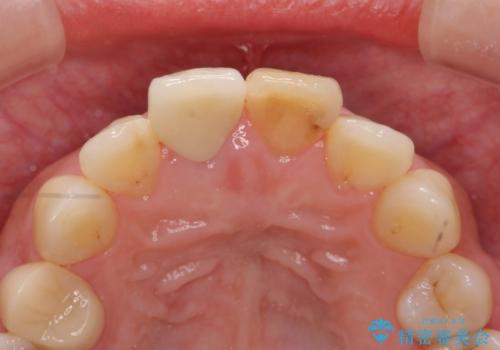

リアルな歯の色調にこだわるオールセラミッククラウン治療

- 歯の神経を除去したのちの、変色の改善を希望され来院されました。

再度根管治療を行ったのちの、オールセラミッククラン治療を計画します。

色調の再現に優れるオールセラミッククラウン スペシャルプランでの治療を希望されました。(保証5年間)

天然歯を再現したリアルな仕上がりに満足いただくことができました。

オールセラミッククラウン スペシャルプランは細やかな色調の再現に優れ、目立つ前歯の審美的な仕上がりがより達成されやすいプランです。